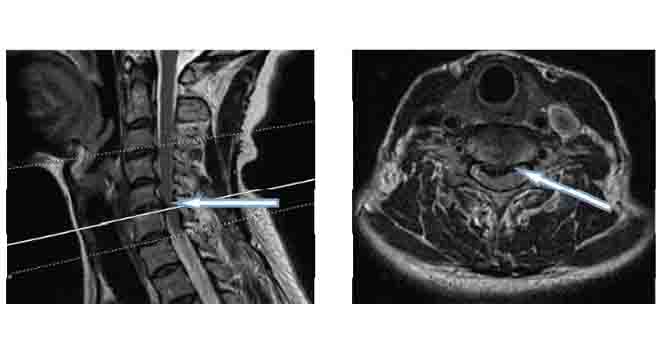

The diagnosis of a cervical herniated disc involves taking a medical history and performing a physical examination of the patient. Physical examination may also involve analysis of the neck movements to determine the source of pain and related injured tissues. Furthermore, various new advanced imaging techniques such as MRI scan, myelogram, CT scan, X-rays, electromyography (EMG) and nerve conduction velocity (NCV) tests, are widely used for accurate diagnosis, as confirmatory tests.